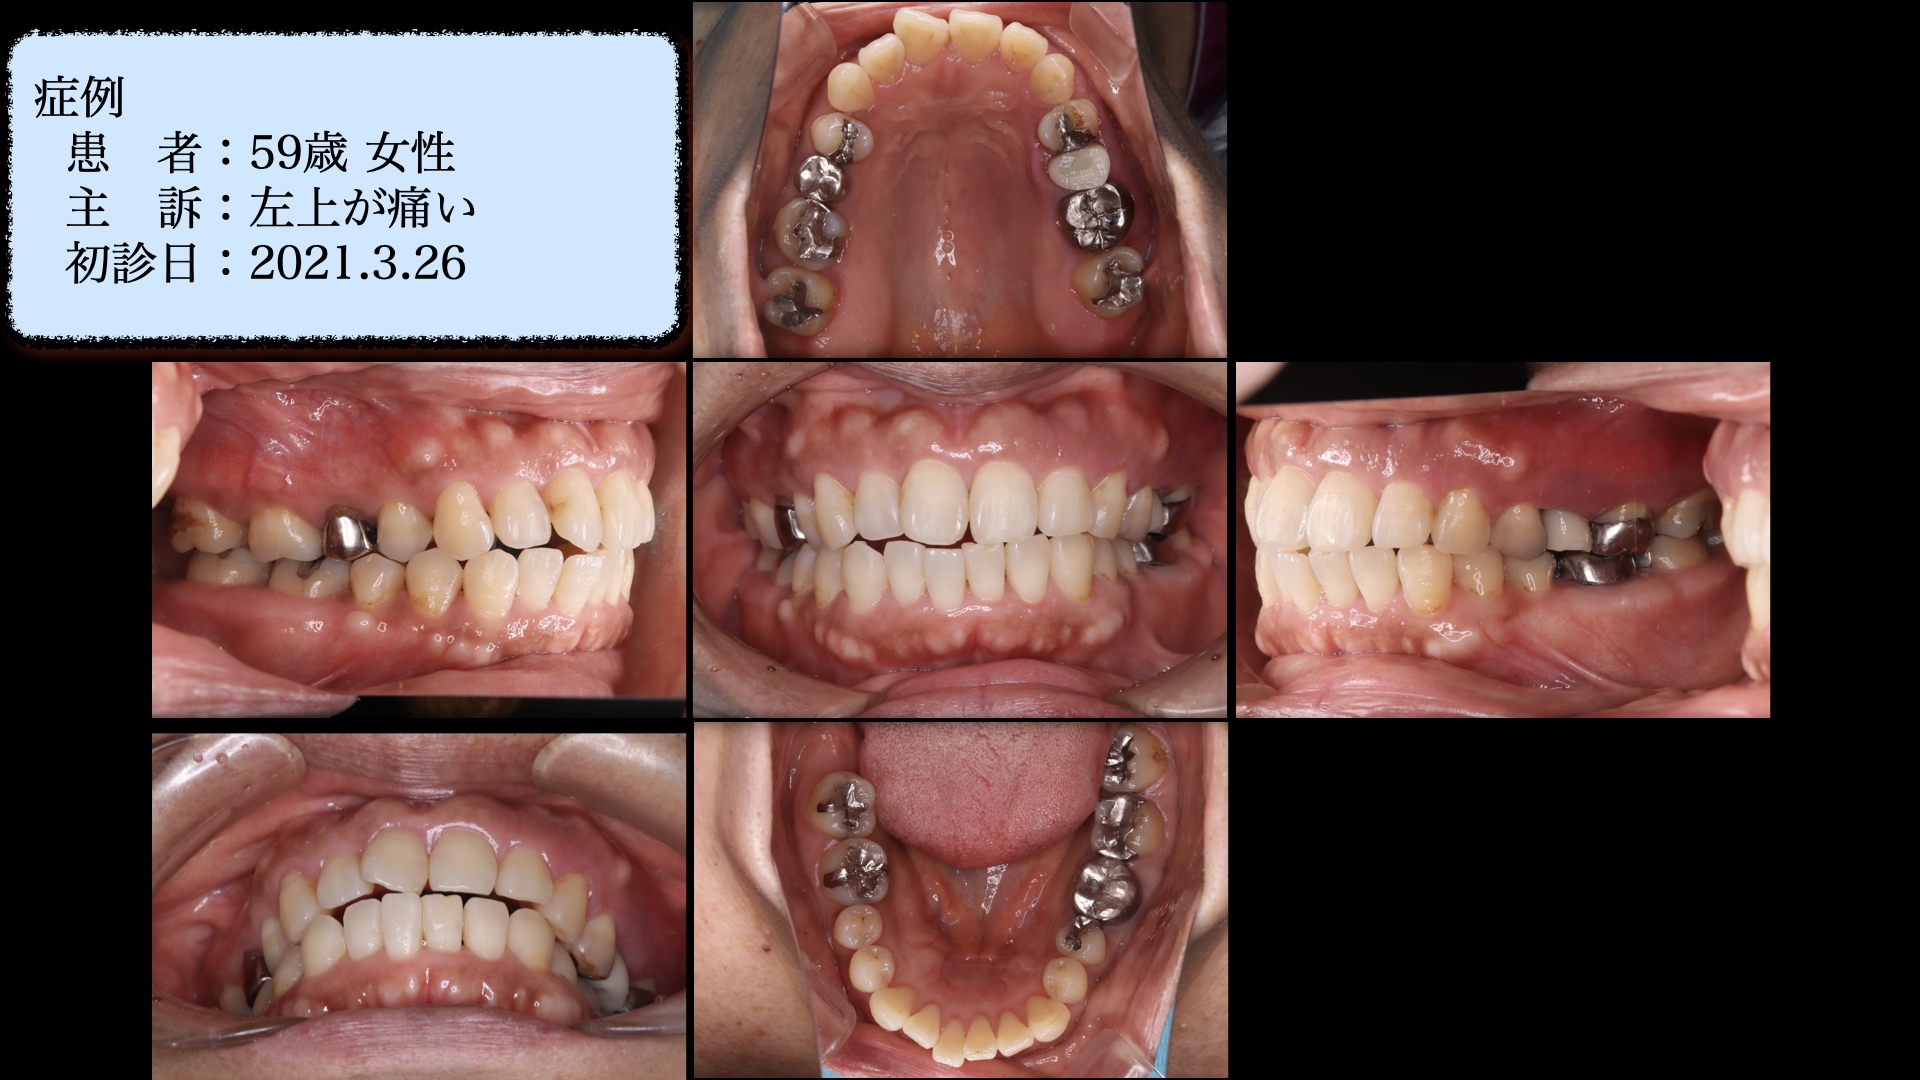

前歯が噛んでおらず、奥歯が壊れてしまったので、矯正・インプラントで治療した症例

| 初診時年齢 | 59歳 |

| 性別 | 女性 |

| 主訴 | 左上が痛い |

| 治療内容 | 矯正治療、インプラント治療、マイクロスコープ |

| 治療回数・期間 | 3年 |

| リスク・副作用 | 将来的な歯周病の再発 |

左上の歯が痛い。ということが主訴で紹介で来られました。左下や真ん中の写真をみてください。

前歯がしっかり噛んでいません。

左上は支えている骨が大きく吸収しています。